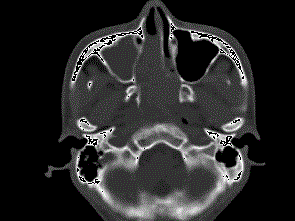

问题 男,20岁,头痛、鼻塞、鼻出血,CT如图所示,最可能诊断为 ( )

选项 A、鼻咽神经纤维瘤 B、鼻咽腺样体增生 C、巨大的鼻息肉 D、鼻咽纤维血管瘤 E、鼻咽癌

答案 D